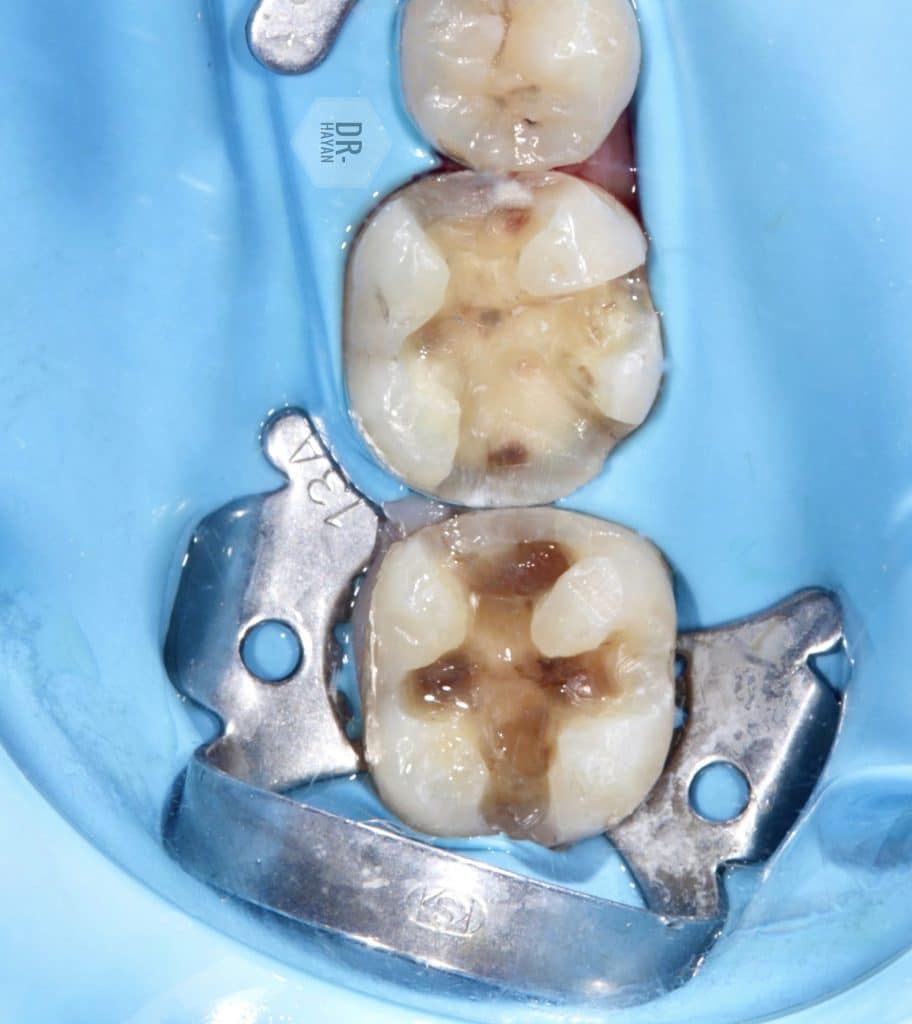

Initial view :

-Old amalgam filling

- Open margin

- recurrent caries

-pain with chewing

After isolation & split dam between 6 ,5